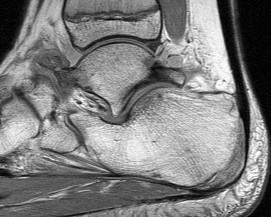

Figures 1a through 1c

Tarsal coalitions occur when primitive mesenchymal cells fail to differentiate and form the

normal articular separations between the tarsal bones of the hindfoot. Overall incidence is difficult to determine because many affected people are minimally symptomatic or asymptomatic. Symptomatic tarsal coalitions typically present in adolescents as a painful flatfoot; however, there are a number of possible presentations, and occasionally symptoms do not appear until adulthood. Most tarsal coalitions are between the calcaneus and the navicular (CN) and the talus and the calcaneus (TC). Although most TC coalitions are across the middle facet, posterior facet coalitions do occur. Plain radiographic evaluation of suspected tarsal coalition is the mainstay for diagnosis. However, coalitions can be bony or fibrous, and making the diagnosis can be difficult. The addition of CT images to distinguish bony definition and MR images to decipher soft tissue can aid in diagnostics. Bony coalitions appear as definite bony bridging between the bones, while fibrous coalitions are suspected when distortion of the bony anatomy is seen. Bony coalitions are best seen on the oblique view (CN) and Harris axial view (TC). There are a number of secondary signs such as the anteater (AE) sign (elongation of the anterior process of the calcaneus as it extends to the navicular as seen on the lateral view [CN]). talar beaking (traction spur of the talar neck thought to result from abnormal stresses as seen on the lateral view [both CN and TN]), and the “C” sign (a continuous cortical contour from the medial talus to the sustentaculum tali [ST]) as seen on the lateral view (TC). A number of newer signs are not as well known, such as a broad mediolateral dimension of the navicular on the anteroposterior (AP) view (the

navicular is wider than the talar head [CN]), nonvisualization of the middle facet on the lateral view (TC), the brick sign (a normal ST is flat, but a distorted ST is enlarged and curved [CN]), and a tapered lateral navicular bone as seen on the AP view (the medial navicular [CN] is much thicker than the lateral navicular).

Figure 1a shows talar beaking (TB), an AE, and an open middle facet (MF). Figure 1b shows a wide navicular (WN), and Figure 1c shows an abnormal articulation between the calcaneus and the navicular, all consistent with a CN coalition.